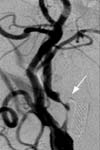

<³»°æµ¿¸ÆÇùÂø>

<¼ö¼úÀü>

¿ìÃø Æí¸¶ºñ¸¦ ÁÖ¼Ò·Î ³»¿øÇÑ È¯ÀÚÀÇ

°æµ¿¸Æ doppler ¼Ò°ß°ú Ç÷°üÃÔ¿µ¼ú ¼Ò°ß(ÁÂÃø

³»°æµ¿¸ÆÀÇ ½ÉÇÑ ÇùÂøÀÌ º¸À̰í ÀÖ´Ù)

<¼ö¼úÈÄ>

ÁÂ) °æµ¿¸Æ È®Àå¼ú ½Ã¼úÀå¸é

¿ì)

°æµ¿¸Æ È®Àå¼ú ¹× ½ºÅÙÆ® »ðÀÔ¼ú ½ÃÇàÈÄ

¼Ò°ß

(Á¼¾ÆÁ®

ÀÖ¾ú´ø ³»°æµ¿¸ÆÀÇ È®ÀåµÇ¾î ÀÖ´Ù.) |